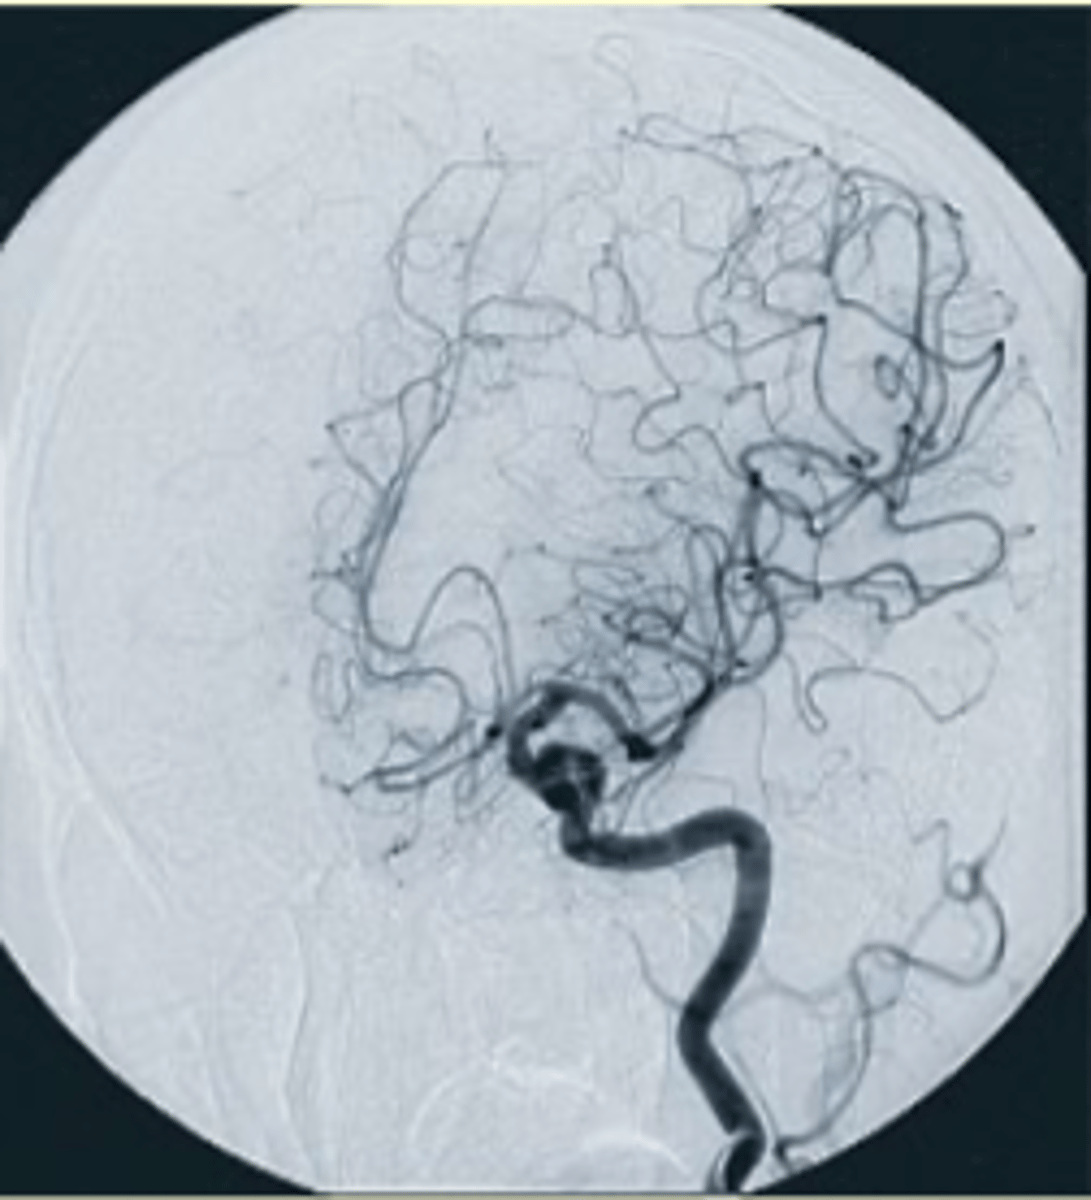

What areas of the body can angiography be performed on?

Most major and minor blood vessels in the head, neck, chest, abdomen, pelvis, and extremities. Lymphatic, urinary, and biliary systems.

What conditions might prompt patients to have studies done for AVM?

Patients who have suffered strokes or have symptoms indicating an AVM.

What is Digital Subtraction Angiography (DSA)?

A technique that requires a digital system to subtract bony and soft tissue anatomy from images, leaving only contrast-filled vessels.